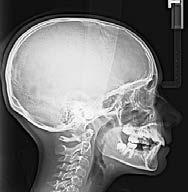

En la radiografía lateral de cráneo se ve el diagnósitico: clase II esqueléti ca, con crecimiento hiperdivergente, mordida profunda anterior (Figura 4).

Estudios radiográficos de inicio en la radiografía lateral de cráneo (Figu ra 5) tenemos la clase II esquelética con un ANB de 7°, hiperdivergencia, aumento de la altura facial anterior, disminución de la altura facial poste rior y proclinación del incisivo supe rior con 1 a plano palatino de 121° e incisivo inferior de 1 a plano mandi bular de 99°.